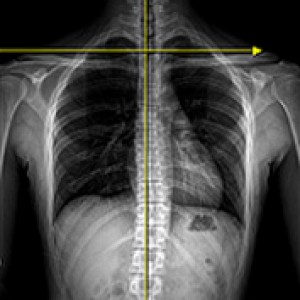

▲ 힘 전달의 균형 유지

▲ 힘 전달의 균형이 깨질 때

성인의 80%~90%에서 골반 부정렬이 발견되었으며,

그 중 3분의 1은 무증상, 3분의 2는 요통, 골반통 등의 증상을 호소한다.

Wolf Schamberger - The Malalignment Syndrome 中